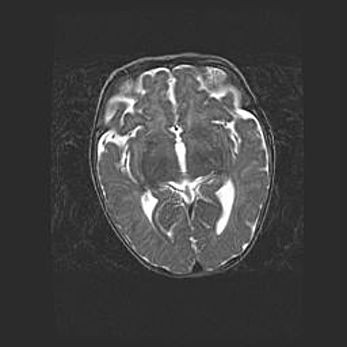

Множественные кисты обоих полушарий головного мозга, наибольшая из них в правой затылочной области. Ассиметричная атрофическая гидроцефалия.

Возраст: 7 месяцев

Вес: 5660 г

Пол: мужской

Окружность головы: 41,5 см

Срок гестации: 28-29 недель

Кисты головного мозга развиваются в результате многоочаговых некрозов вещества мозга и возникают вследствие перенесенной перинатальной инфекции, менингитов, энцефалитов, асфиксии, родовой травмы, расстройств мозгового кровообращения различного генеза. Образованию кист в веществе головного мозга плодов и новорожденных способствуют такие факторы, как высокое содержание в нем воды, недостаточная (или отсутствие) миелинизация и слабая астроглиальная реакция на повреждение.

Кисты могут сочетаться с гидроцефалией и другими поражениями головного мозга.